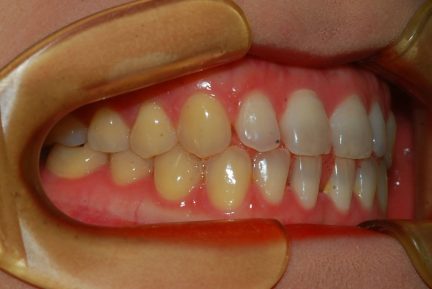

Classe III, articulé postérieur, arcades étroites, arcades asymétriques, déviation de la ligne médiane mandibulaire, décalage de la ligne médiane, rotations, espacement

État initial